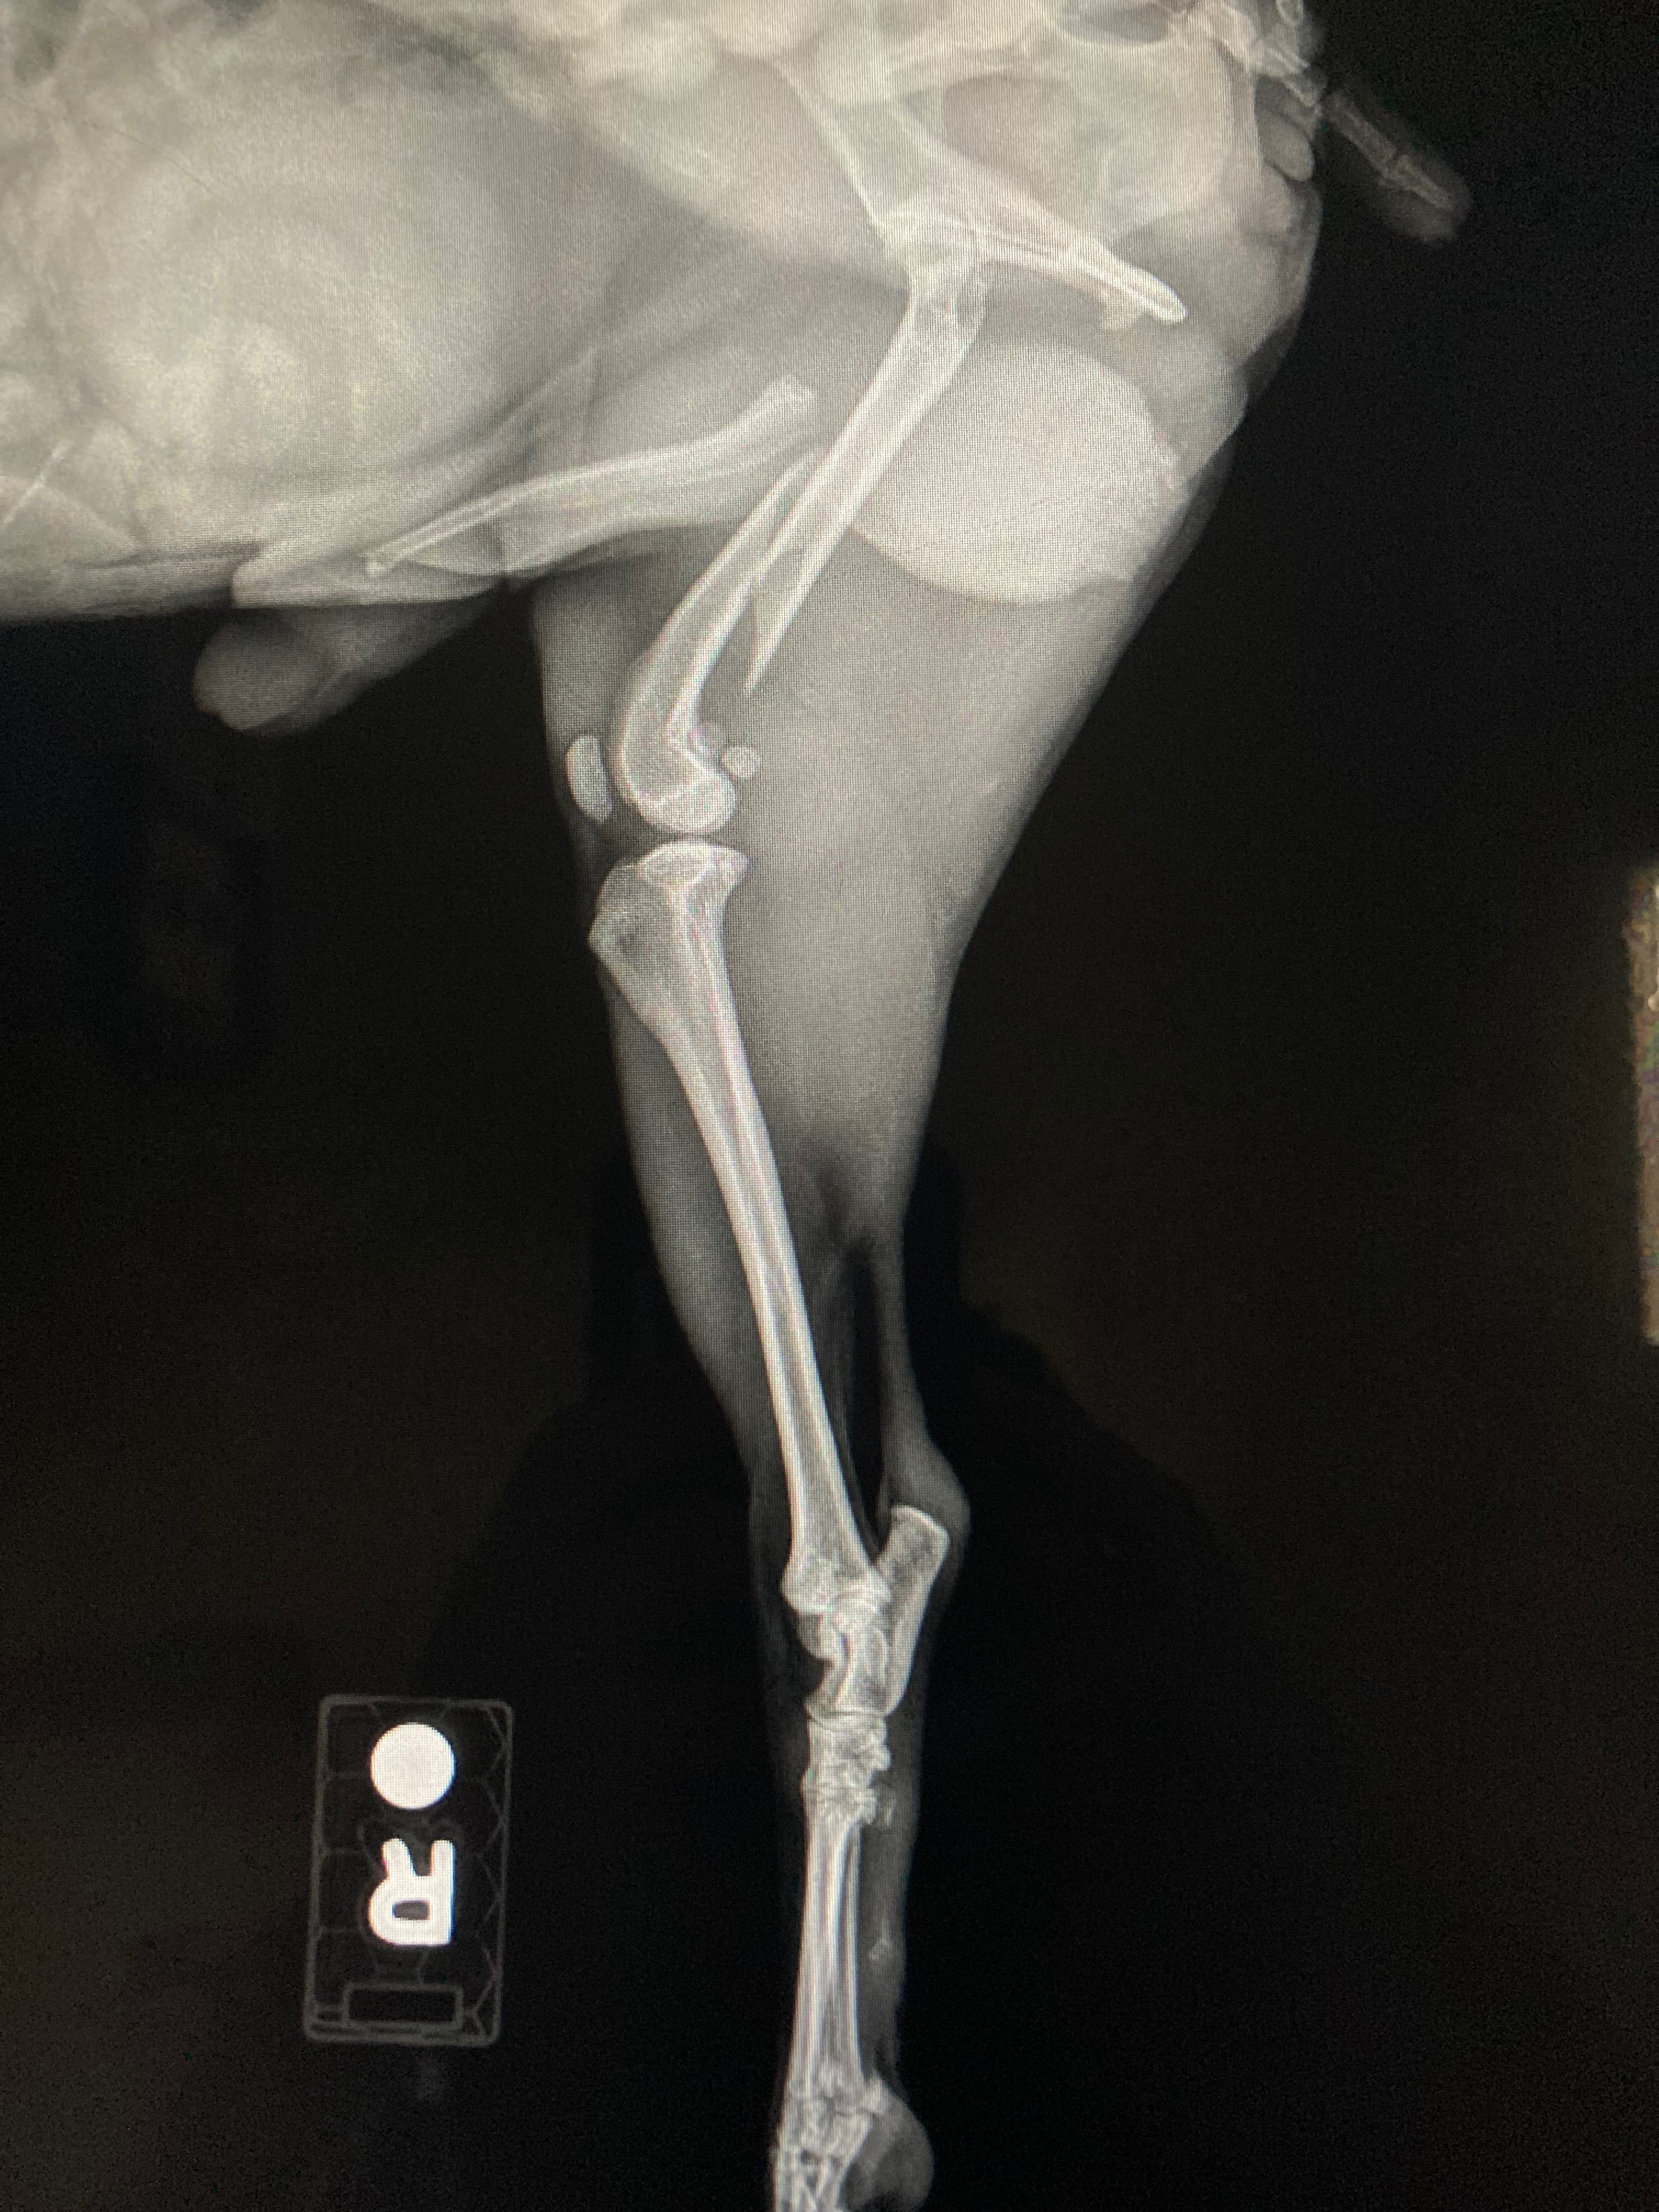

Update: 3:25a.m. Roscoe has a broken femur. His thigh is swollen and he’s given pain meds for now. Will need to take him to specialty hospital for a board certified surgeon evaluation in just a few hours. I’m told cost for surgery is between $8000 to $10,000, not including other miscellaneous fees. Either that I’m told to amputate his leg to save money. Seriously?!!! I’m all out of tears. I refuse to have his leg amputated because I don’t have the funds.

He lost his footing and fell today while he was on the couch and landed on his right hip. While we wait in the emergency room, he is whimpering in pain. His leg is bent the wrong way and I’m afraid to move it. He yelps when I tried to straighten it.